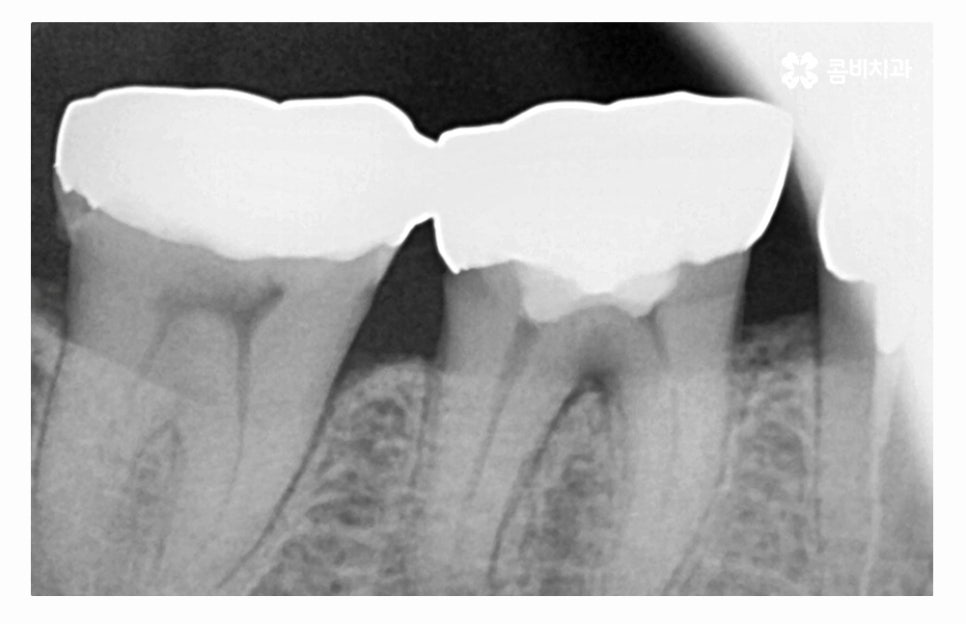

나이가 들면서 보철물 교체 시기를 놓쳐 과거에 충치 치료를 했던

부위에 2차 충치가 발생되는 사례도 많기 때문에 인레이, 크라운 치료 등을

받으셨다면 오랜 기간이 지난 경우에는 검진을 받아보시고

필요시 교체를 해야 하며, 오늘 보여드린 사례와 같이

치아 속은 눈으로 확인이 어렵기 때문에 주기적인

치과 검진을 받는 것이 자연치아를 지키는 방법이라고 할 수 있어요.